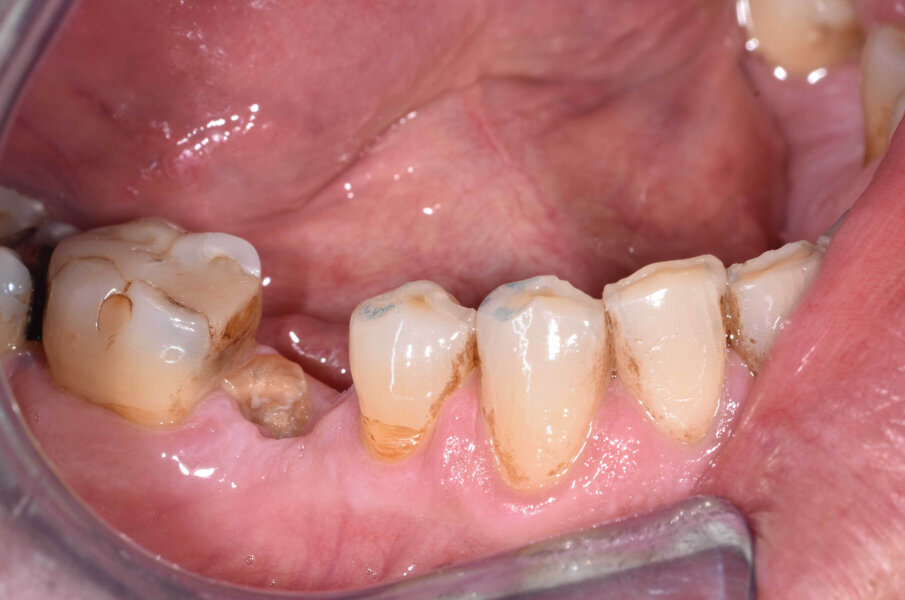

G. I. paziente di anni 50, si presenta alla nostra osservazione con una frattura longitudinale della radice dell’elemento 4.5 dovuta a infiltrazione cariosa della vecchia corona protesica. Questa situazione ha provocato nell’osso alveolare del paziente una grossa lesione che è andata ad interessare anche la corticale vestibolare. Per poter sostituire la radice con un impianto sarebbe necessario un intervento di chirurgia ossea rigenerativa ma un’alternativa meno invasiva è la rigenerazione del tessuto osseo ottenuta tramite l’estrusione forzata dell’elemento che rigenera osso durante la sua lenta migrazione grazie al legamento parodontale. In accordo con il paziente, dopo opportuna spiegazione dei benefici e dei tempi dell’approccio con estrusione ortodontica, si decide di procedere con questo iter evitando così l’intervento di rigenerativa.

L’estrusione completa del frammento ha richiesto un tempo di 6 mesi, durante i quali è stata modificata più volte l’inclinazione della molla per evitare che il movimento diventasse ortogonale al segmento e mantenere la traiettoria prevista. Così facendo, è stato possibile rigenerare naturalmente l’intero alveolo e inserire, dopo 3 mesi di ulteriore maturazione del tessuto, in un contesto osseo ideale e perfettamente rigenerato un impianto Syra (Sweden & Martina) di diametro 4.25 mm e lungo 11 mm.

Dopo 3 mesi dall’inserimento implantare è stato possibile prendere un’impronta e di precisione e realizzare una corona singola avvitata.